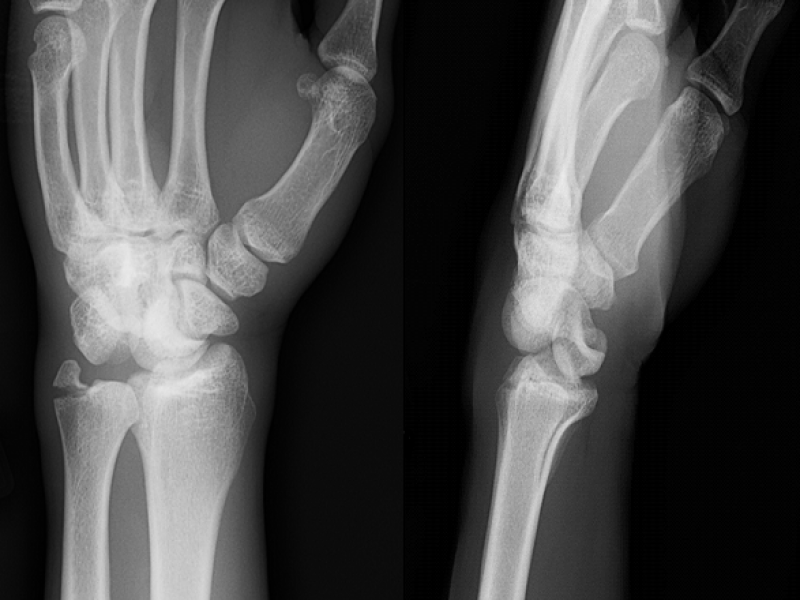

A 24 yo M presents after a fall from a bike onto an